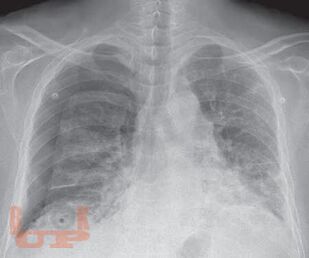

First textbook about pleural disease written and edited by Indian authors. First pleural textbook which has contributions from multiple authors. Textbook of pleural disease which has been authored by multiple specialtiesa unique feature where each chapter has been written by the concerned specialists, e.g., pleural disease in kidney disease by nephrologist, hepatic hydrothorax by hepatologist, and pleural disease in gynecological disorder by gynecologist. Every aspect of pleura from embryology, anatomy, physiology, and radiological diagnosis has been covered in detail. Role of ultrasonography in pleura, which is now a vital tool for point-of-care management has been described in detail. High-quality pleural imaging and its highlights are shown in concerned chapters Pathophysiologic basis of pleural diseases has been discussed with each specific disease. Concise algorithm summarizing disease management has been clearly depicted. Updated treatment as per recent guidelines has been incorporated. The topics in pleural diseases have been written by eminent chest physicians all over India. A special chapter describes pleural diseases in COVID, in the post pandemic era. Being a Lung Transplant center, a special chapter on overview on pleura issues in lung transplant has been elaborated.